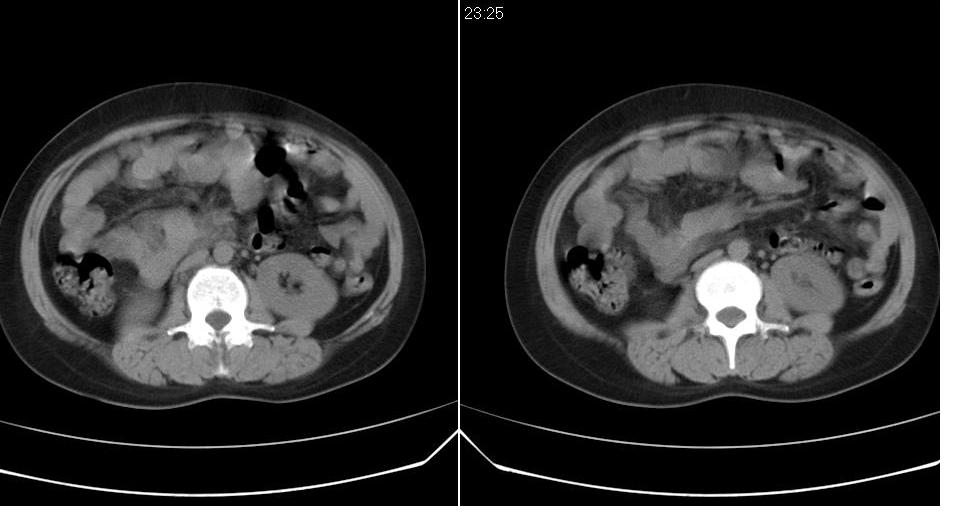

女 35岁,下腹部坠感疼,其它病史不详。图象顺序有点乱。

定位于盆腔附件,有囊性密度,有脂肪密度、还有骨密度;应该是比较典型的卵巢畸胎瘤。